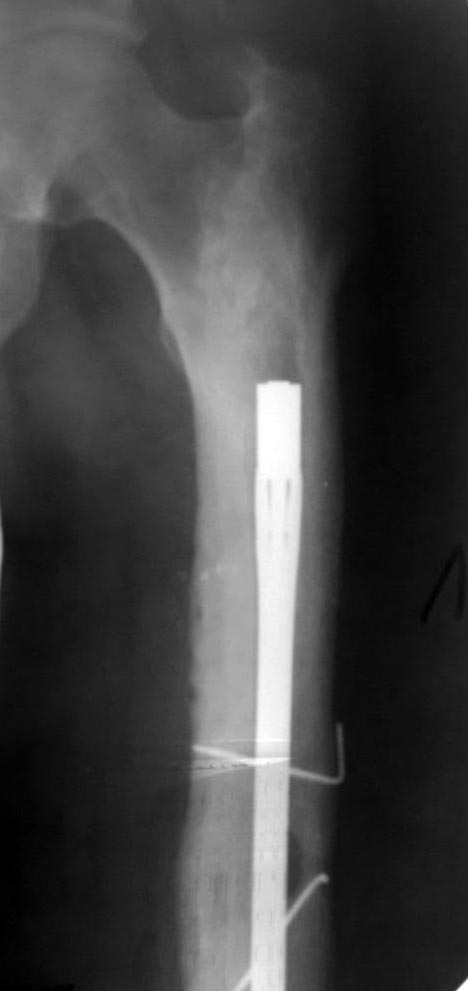

Доброго дня коллеги!поступает пациент, оперирован 9 лет назад,

последний месяц начали беспокоить боли в коленном суставе при ходьбе

последний месяц начали беспокоить боли в коленном суставе при

ходьбе!Визуально отек коленного сустава,синовит, ограничение и сгибания

и разгибания. наш план зайти антеградно при помощи эопа и всетаки

попытаться его удалить. Сейчас ищем инструмент через москву. на потоке

это никогда не ставили. хотелось бы услышать мнения, советы.